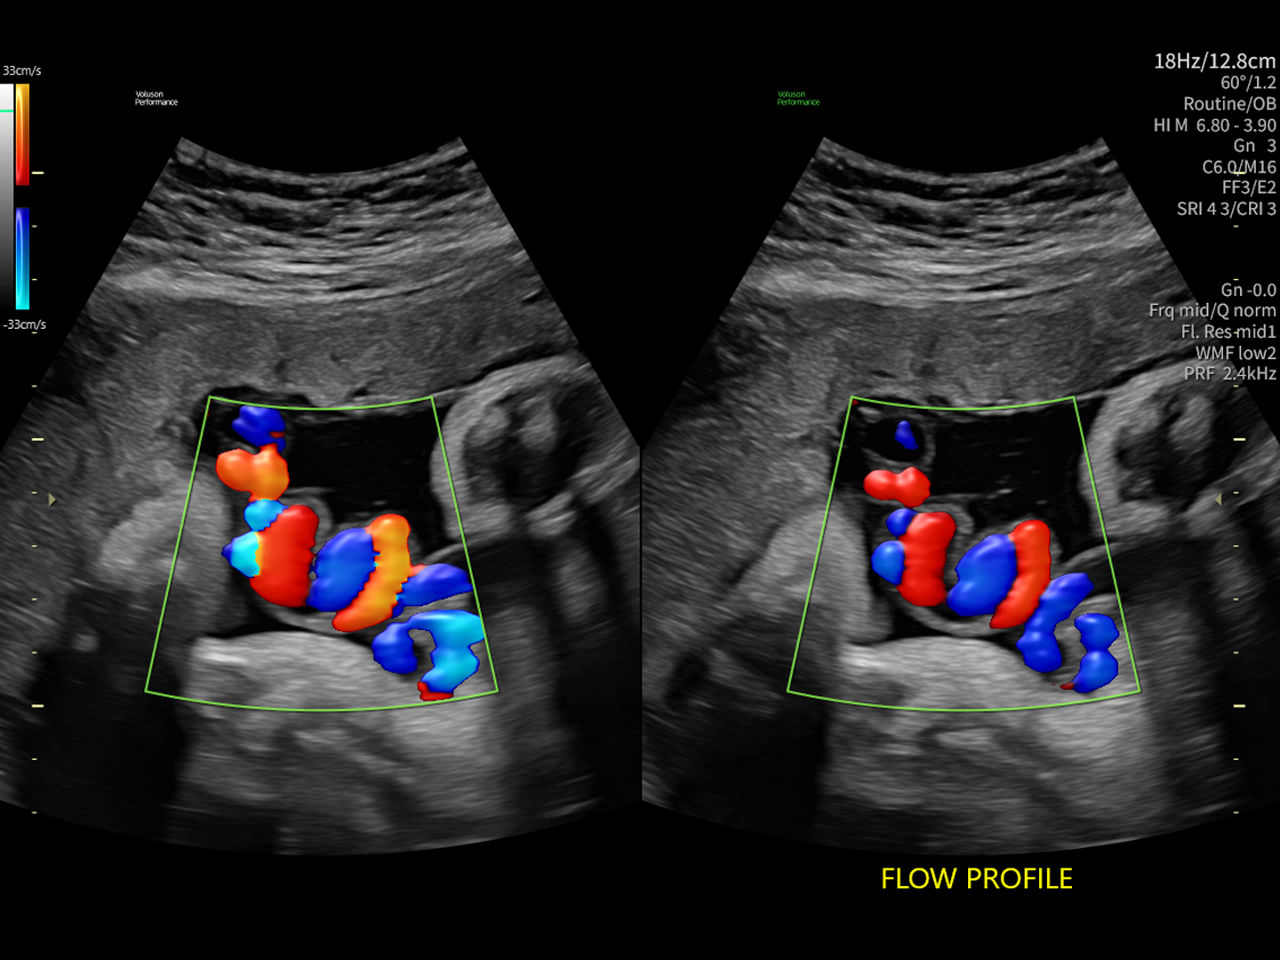

Flow Profiles

Go with the flow

Flow Profiles dramatically simplifies color and spectral Doppler optimization by utilizing predefined, optimized settings. Flow Profiles can reduce Doppler exam time by up to 56%.